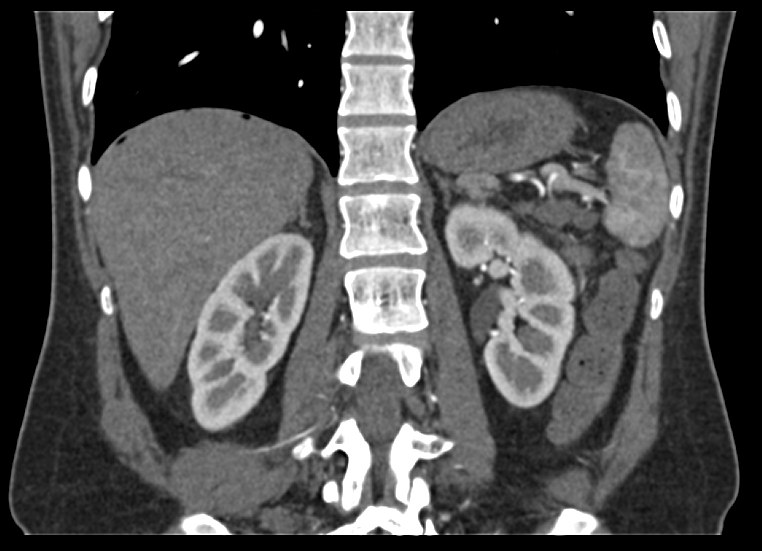

- Количество срезов: 64